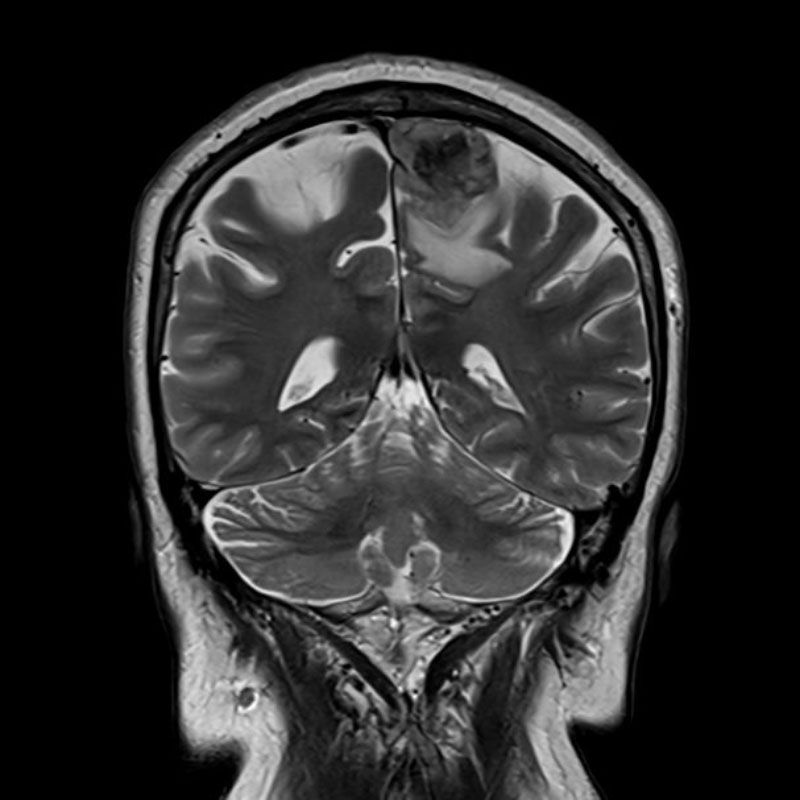

696

'25年11月

70代

眼窩腫瘍

頭蓋内腫瘍摘出術